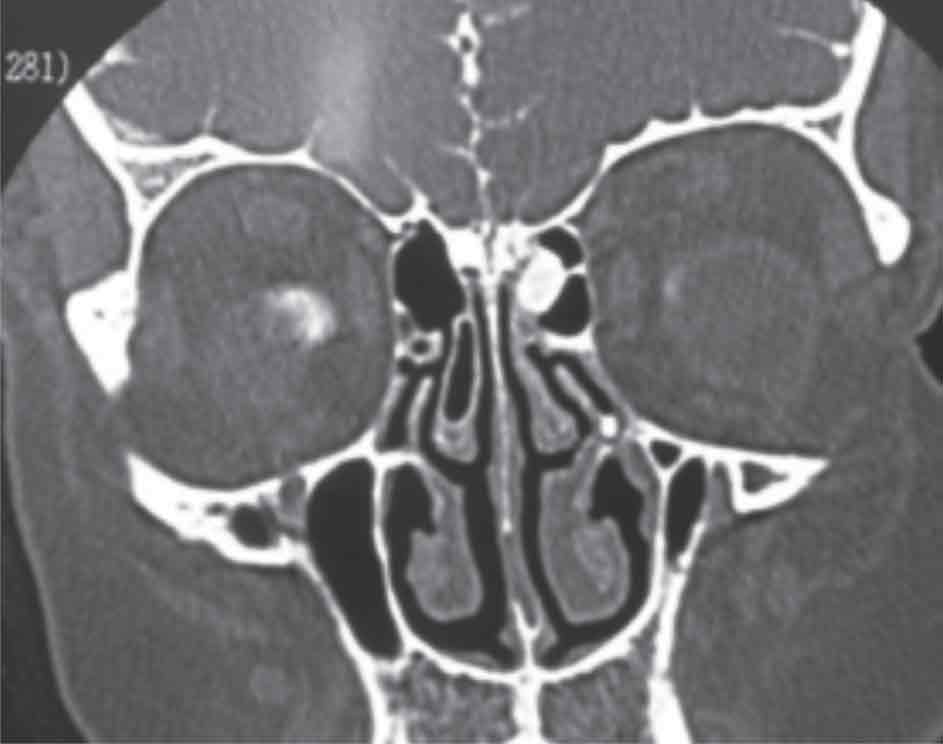

الشكل (2) يبدي التصوير المقطعي المحوسب

كسرا صريحا في سقف الغربال الأيمن

يبدي التصوير المقطعي المحوسب وجود تفرق اتصال أو كسر صريح في قاعدة القحف الأمامية (الشكل 2) إما بمنطقة الصفيحة المصفوية cribriform وإما الصفيحة الجانبية lateral lamella وإما النقرة الغربالية fovea ethmoidalis، وأحياناً على الصفيحة الخلفية للجيب الجبهي أو في سقف الجيب الوتدي أو جداره الجانبي .